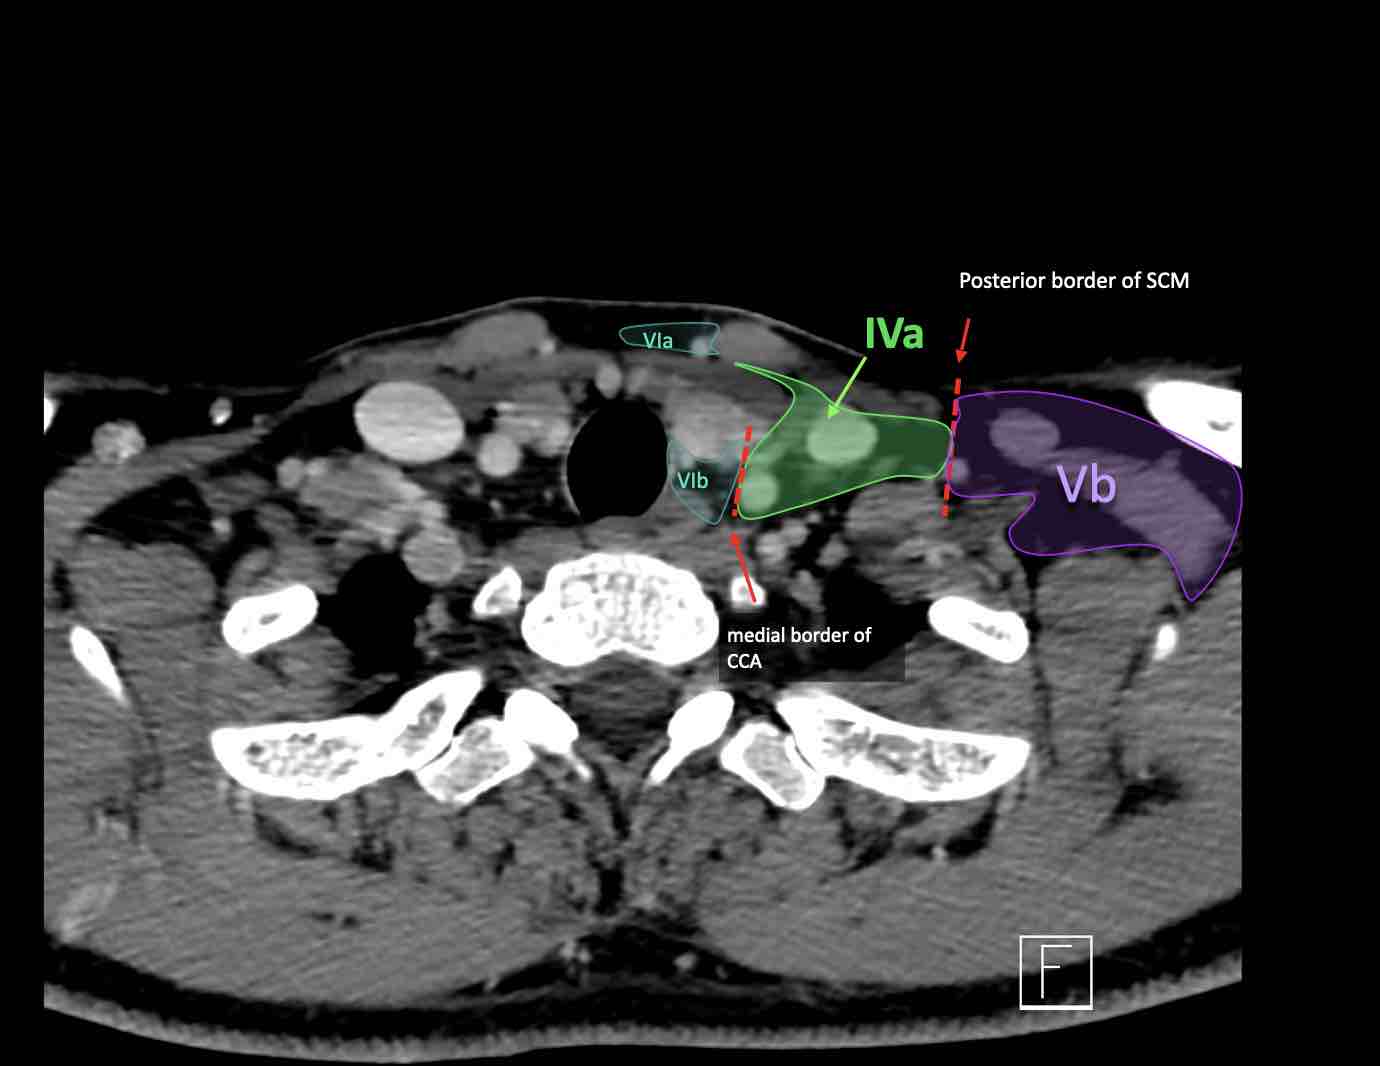

IV – Tĩnh mạch cảnh dưới và hố thượng đòn trong

Ranh giới giữa tầng IVa và IVb được xác định tùy ý tại vị trí 2 cm phía trên khớp ức đòn.

Tầng IVa

Các hạch này có nguy cơ chứa di căn từ các ung thư hạ hầu, thanh quản, tuyến giáp và thực quản cổ.

Hiếm gặp hơn, di căn từ khoang miệng trước có thể biểu hiện tại vị trí này với tổn thương hạch gần tối thiểu hoặc không có.

Tầng IVb

Các hạch này có nguy cơ chứa di căn từ các ung thư hạ hầu, thanh quản dưới thanh môn, khí quản, tuyến giáp và thực quản cổ.

V – Tam giác cổ sau và hố thượng đòn

Tầng V chứa các hạch của nhóm tam giác cổ sau nằm ở phía sau cơ ức đòn chũm, xung quanh phần dưới của thần kinh phụ gai sống và các mạch máu cổ ngang.

Các hạch bạch huyết ở tầng V thường liên quan nhất đến các ung thư nguyên phát của vòm hầu, hầu miệng, các cấu trúc da vùng da đầu phía sau và tuyến giáp.

Tầng Vc – Hố thượng đòn

Tầng này chứa các hạch thượng đòn bên nằm trong phần tiếp nối của các hạch tam giác cổ sau (tầng Va và Vb) từ các mạch máu cổ ngang xuống đến giới hạn được xác định tùy ý tại vị trí 2 cm phía trên cán ức.

Tầng này tương ứng một phần với vùng được gọi là hố thượng đòn.

Tầng Vc nhận các bạch mạch hướng tâm từ các hạch tam giác cổ sau (tầng Va và Vb) và thường liên quan hơn đến các khối u vòm hầu [1].